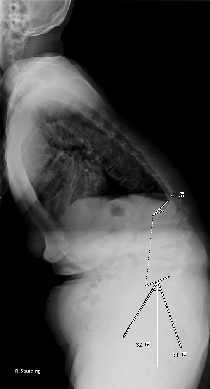

思春期特発性側弯症の全脊椎レントゲンで背骨が大きくSの字に曲がっています。最も曲がっている箇所は80°で、高度側弯に分類されます。後方からの脊柱側弯矯正術で真っ直ぐになっています。

また、側弯の患者さんは一般的にフラットバックと言って背骨の生理的後弯(背中の丸み)が失われています。この症例も胸椎後弯角は5°で典型的なフラットバックを呈しています(正常は20°~30°程度です)。この影響は頸椎の形態にも影響を及ぼし、この症例も頸椎が既に後弯(正常は前弯)しています。(黄色矢印)

ストレートネックという頸椎の前弯が消失して頸部の愁訴が出現する病態は広く知られていますが、更に変形が進行した頸椎と考えて下さい。

以前はこのフラットバック(生理的胸椎後弯の消失)を治すことは困難でしたが、当院では手術方法の様々な工夫により生理的胸椎後弯の復元を行っております。この症例は術後に胸椎後弯角が26°と改善しており、生理的な胸椎後弯が形成されています。さらに頸椎後弯にも良い影響を及ぼし、術後は頸椎前弯化が得られつつあるのが分かります。(黄色矢印)

他、側弯変形は必ず大なり小なりの回旋変形を伴います。脊柱の回旋変形は胸郭(肋骨)の回旋につながり、これにより側弯の患者さんは背中の片方が出っ張っています(多くは右)。リブハンプと言いますが、脊柱変形矯正によりこの回旋変形も改善します。この症例も術前に肋骨がかなり隆起していますが、術後にこの隆起がかなり減じているのが分かります。(赤矢印)